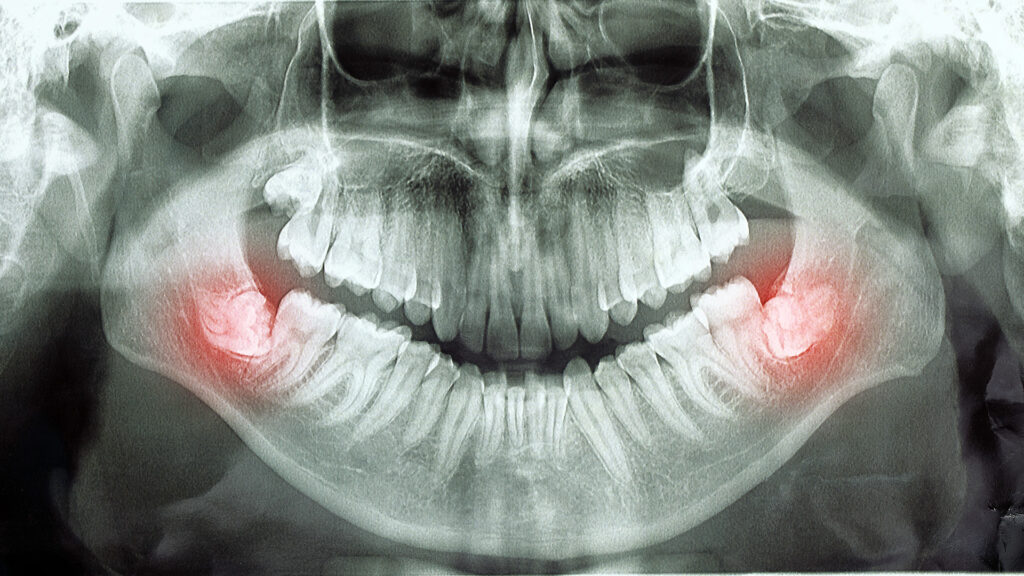

Wisdom teeth, or third molars, are the last adult teeth to develop and erupt. For many people, these teeth do not have adequate room to come in properly, which can lead to issues that affect comfort, gum health, and tooth alignment. Knowing when removal is recommended allows you to prevent complications such as pain, infection, crowding, and damage to nearby teeth. This page explains why you may need your wisdom teeth removed, what is the purpose for wisdom teeth, and addresses the common question of why do we need wisdom teeth, so you can make informed decisions about evaluation and timing.

Wisdom teeth are located at the very back of the upper and lower jaws, behind the second molars. Historically, they aided in chewing tougher foods, but modern diets and generally smaller jaws mean these teeth often don’t have enough space to grow straight and fully erupt. Most people have four wisdom teeth, though some may have fewer—or none at all. When considering what is the purpose for wisdom teeth, it helps to recognize that their evolutionary role in grinding fibrous foods is less relevant today, which partly explains why you may need your wisdom teeth removed.

These molars typically begin to emerge between ages 17 and 25, but the timeline varies. Some third molars remain beneath the gums or within the jawbone. Early evaluation in the late teenage years gives your dental and orthodontic team time to monitor their development, assess available space, and plan to protect your alignment and long-term oral health. Asking why we need wisdom teeth is common; for many individuals, the lack of space and cleaning challenges mean these teeth can become liabilities rather than assets.

Because of their position and angulation, wisdom teeth can erupt in several ways: straight up, tipped toward neighboring teeth, angled toward the cheek or tongue, or lying horizontally under the gums. Their location makes it challenging to brush and floss effectively. When they are partially erupted or impacted, plaque and bacteria can accumulate around the gum tissue, increasing the risk of decay, inflammation, and infection. These factors contribute to why you may need your wisdom teeth removed, even if you understand what is the purpose for wisdom teeth from a historical perspective.

Impaction and structural damage: Impaction occurs when a wisdom tooth is blocked from erupting correctly by bone, gum tissue, or adjacent teeth. Impacted teeth may press against the second molars, damage roots, or contribute to bone loss. They can also form cysts or, more rarely, tumors that affect jaw structures. Food and bacteria often become trapped beneath the gum flap over an impacted tooth, leading to irritation and recurrent infections. Removing impacted wisdom teeth can prevent pain and help protect the integrity of your teeth and jawbone, which explains why you may need your wisdom teeth removed despite wondering why we need wisdom teeth.

During your evaluation, your oral surgery team will examine your mouth and review panoramic X-rays or 3D imaging to assess tooth position, root development, and available space. They consider your age, symptoms, gum health, and orthodontic history to determine whether observation, improved hygiene strategies, or removal is the best approach. Not all wisdom teeth need to be removed; in some cases, careful monitoring is appropriate if the teeth are healthy, fully erupted, and easy to keep clean. This balanced approach addresses what is the purpose for wisdom teeth and helps answer why we need wisdom teeth in modern oral care.